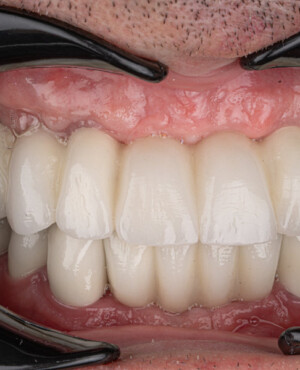

Un posibil dezavantaj îl reprezintă riscul apariției unor fisuri sau crăpături în stratul ceramic, precum și expunerea marginii metalice la baza coroanei, ceea ce poate determina o colorare închisă a gingiilor în zona respectivă. Pentru a elimina acest efect, în stomatologia modernă se fabrică coronițe metaloceramice cu umăr (margine) integral ceramic, care previne contactul direct al gingiilor cu metalul.

Un alt avantaj este etanșeitatea excelentă a protezelor, oferită de designul bordurii la nivelul marginilor de contact cu gingiile și de posibilitatea înlocuirii marginii metalice cu ceramică, ceea ce prelungește durata de viață a coroanei.

Prin realizarea coronițelor în conformitate cu parametrii exacți ai dinților protezați, această tehnologie asigură atât estetica, cât și funcționalitatea necesare, conferind un aspect natural întregii dentații.